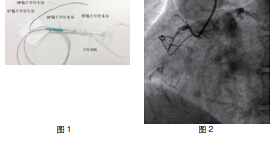

冠状动脉造影发现:LAD中段严重狭窄,可见间隔支到RCA侧枝循环。RCA中段次全闭塞,远端完全闭塞(图1~2)。患者为劳力性心绞痛, RCA为CTO病变,近日症状加重考虑可能为LAD病变进展所致,LAD可能是此次的罪犯血管。但LAD通过间隔支侧枝给RCA供血,治疗LAD风险较大,故此次拟先开通完全闭塞的RCA后择期行前降支PCI 术。

患者RCA为完全闭塞病变,用6F.EBU 3.5导引导管经股动脉对侧造影显示间隔支到RCA远端的侧枝循环,如正向无法开通右冠状动脉可改逆向开通。用JR6F-4导引导管两条pilot-50导引导丝在微导管支持下,用平行导丝技术通过闭塞病变(图3)。分别用Sprinter 1.5 mm×15 mm和2.5 mm×15 mm球囊扩张后RCA开口出现严重夹层,在RCA近端置入Partner 3.0 mm×36 mm支架(图4)。但支架远端仍有严重狭窄,IVUS证实RCA全程弥漫病变,用原2.5 mm球囊扩张后支架远端后,支架远端出现螺旋夹层。拟通过近端支架置入另一Partner 2.75 mm×36 mm支架,但支架无法通过近端支架,头端卡在第一个支架内,在反复用力推送过程中导引导管、导丝自RCA中脱出、将支架球囊弹出,支架球囊撤出体外后发现支架已脱落。透视RCA开口至桡动脉全程,及导引导管内,未发现脱落支架。迅速将原JR4导引导管到位,置BMW导丝到RCA远端,保证RCA开通(图5),IVUS证实导丝全程在真腔内。用原2.5 mm球囊扩张RCA远端以便器械通过(图6)。血管内超声检查提示RCA中段螺旋夹层,撕裂深及血管外膜(图7)。右冠近端支架膨胀、贴壁良好(图8)。将超声导管回撤至右冠状动脉开口处,可见脱落支架卡在右冠状动脉近端支架开口处(图9)。拟取出支架,为预防取出支架过程中RCA急性闭塞,在RCA远端置入BuMA 2.5 mm×30 mm和3.0 mm×30 mm支架,近端支架和原RCA开口处支架未连接(图10)。将Snare圈套器经原作为对侧造影的6F.EBU 3.5导引导管伸出(图11),调整位置,将脱落的支架套住。同时将RCA内的导丝保留,RCA近端支架内预置一3.0 mm×10 mm高压球囊,以保护在取出脱落支架时RCA开口处支架不受影响(图12)。在回撤圈套器时遇到较大阻力,反复推拉,在取出脱落支架的同时将置入RCA开口已释放的的Partner 3.0 mm×36 mm支架带出(图13~14)。RCA开口出现螺旋夹层,但未闭塞。立刻重新置入导丝,IVUS证实导丝在真腔内,在RCA近端分别置入BuMA3.0 mm×25 mm和3.5 mm×20 mm支架,RCA无残余狭窄,血流TIMI3级(图15)。